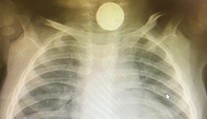

Bábätko mesiace odmietalo stravu, lekári nevedeli prečo. Všetko odhalil až röntgen Róbert Ďurkáč 14. 1. 2021